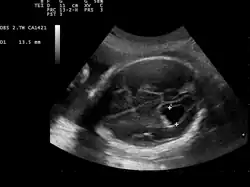

| Prenatal ultrasound showing a well defined hypoechoic lesion corresponding to a choroid plexus cyst | |

Choroid plexus cysts (CPCs) are cysts that occur within choroid plexus of the brain. They are the most common type of intraventricular cyst,[1] occurring in 1% of all pregnancies.[2]

CPCs can form within this structure and come from fluid trapped within this spongy layer of cells, much like a soap bubble or a blister. CPCs are often called "soft signs" or fetal ultrasound "markers" because some studies have found a weak association between CPCs and fetal chromosome abnormalities.